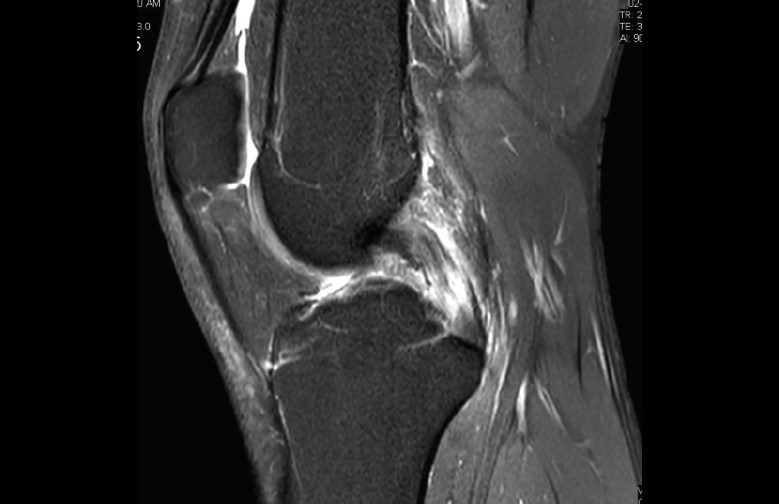

1.2. Ligamentos

Se visualizan como estructuras lineales hipointensas en todas las secuencias.

1.2.1. Ligamentos laterales

Figura 36. Corte de secuencia coronal T2 Fat-Sat: ligamentos colaterales normales.

Ligamento lateral interno (LLI) y ligamento lateral externo (LLE) (Figuras 36, 37, 38 y 39).

1.2.2. Ligamento cruzado anterior (LCA) (Figuras 40, 41, 42, 43 y 44)

Figura 40. Corte de secuencia sagital T2 Fat-Sat de resonancia magnética de rodilla: ligamento cruzado anterior normal.